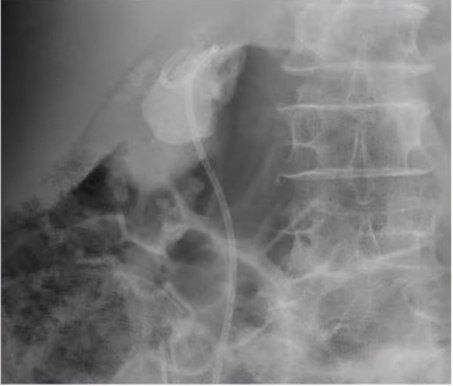

Tại phòng khám Ngoại Tiết Niệu Bệnh viện Đa khoa Xuyên Á, người bệnh được thăm khám và chụp CT, xét nghiệm. Kết quả cận lâm sàng ghi nhận bà T. bị sỏi san hô có đường kính 5cm, sỏi từ bể thận bên phải có nhiều nhánh vào đài thận và hầu hết các đài thận còn lại đều có sỏi, gây nhiễm trùng đường tiết niệu.